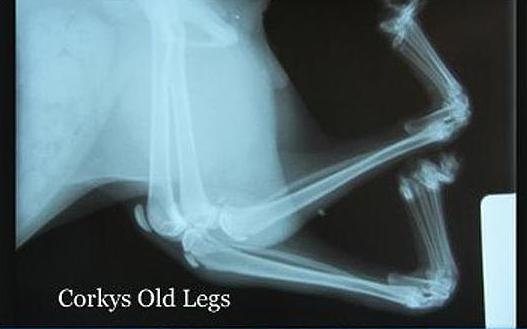

Ο 9 μηνών Corky γεννήθηκε με τα δύο πόδια του… σε αντίθετη φορά από το φυσιολογικό! Τα πίσω πόδια του ήταν γυρισμένα… ανάποδα και τώρα, αφού υποβλήθηκε σε μια πρωτοποριακή επέμβαση στο κέντρο Cats Cradle Shelter στη βόρεια Ντακότα, άρχισε να μαθαίνει να περπατά!

Εθελοντές του κέντρου τον βρήκαν να σέρνεται στους δρόμους της Μινεσότα και τον μετέφεραν στο κέντρο περίθαλψης. Ύστερα από πέντε ώρες στο χειρουργείο τα πόδια του ήταν… στη σωστή τους θέση!